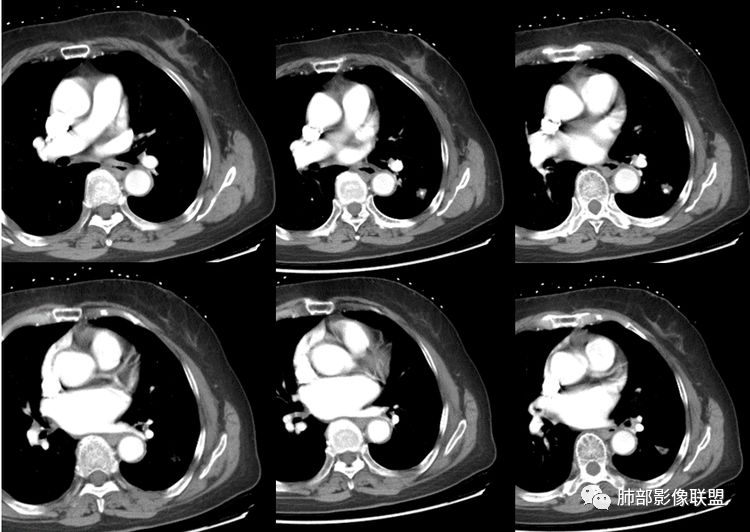

看了薄层我也倾向于恶性肿瘤。叶间裂牵拉比较明显了,分叶,胸膜凹陷,周围清晰磨玻璃,支气管也闭了。

冠状薄层像是恶性南边:

这属于瘢痕癌,有炎性特点,有长索条影,有钙化,血管进入,比较自如,边缘似乎有点毛糙,有长索条影,有恶性特点,大家都关注钙化了,关注边缘收缩了,

结果:微浸润性腺癌

南边:这类病变,其实我们读了很多了。属于什么样的病变,属于瘢痕癌。我先标注给大家看一下,这个良恶性特点在哪里:

3.如我们无视这一钙化灶,结节影却似乎表现出另一副面孔,实性成份较多,边缘不规则,居然有磨玻璃有分叶、有异常供血、有棘状突起有胸膜牵拉等。病灶孤立,不像错构瘤静悄悄悬挂血管旁,亦未如结核球那样多卫星灶。

4.注意增强扫描,实性部分有较明显强化,这无论在结核球或是错构瘤都非常少见。